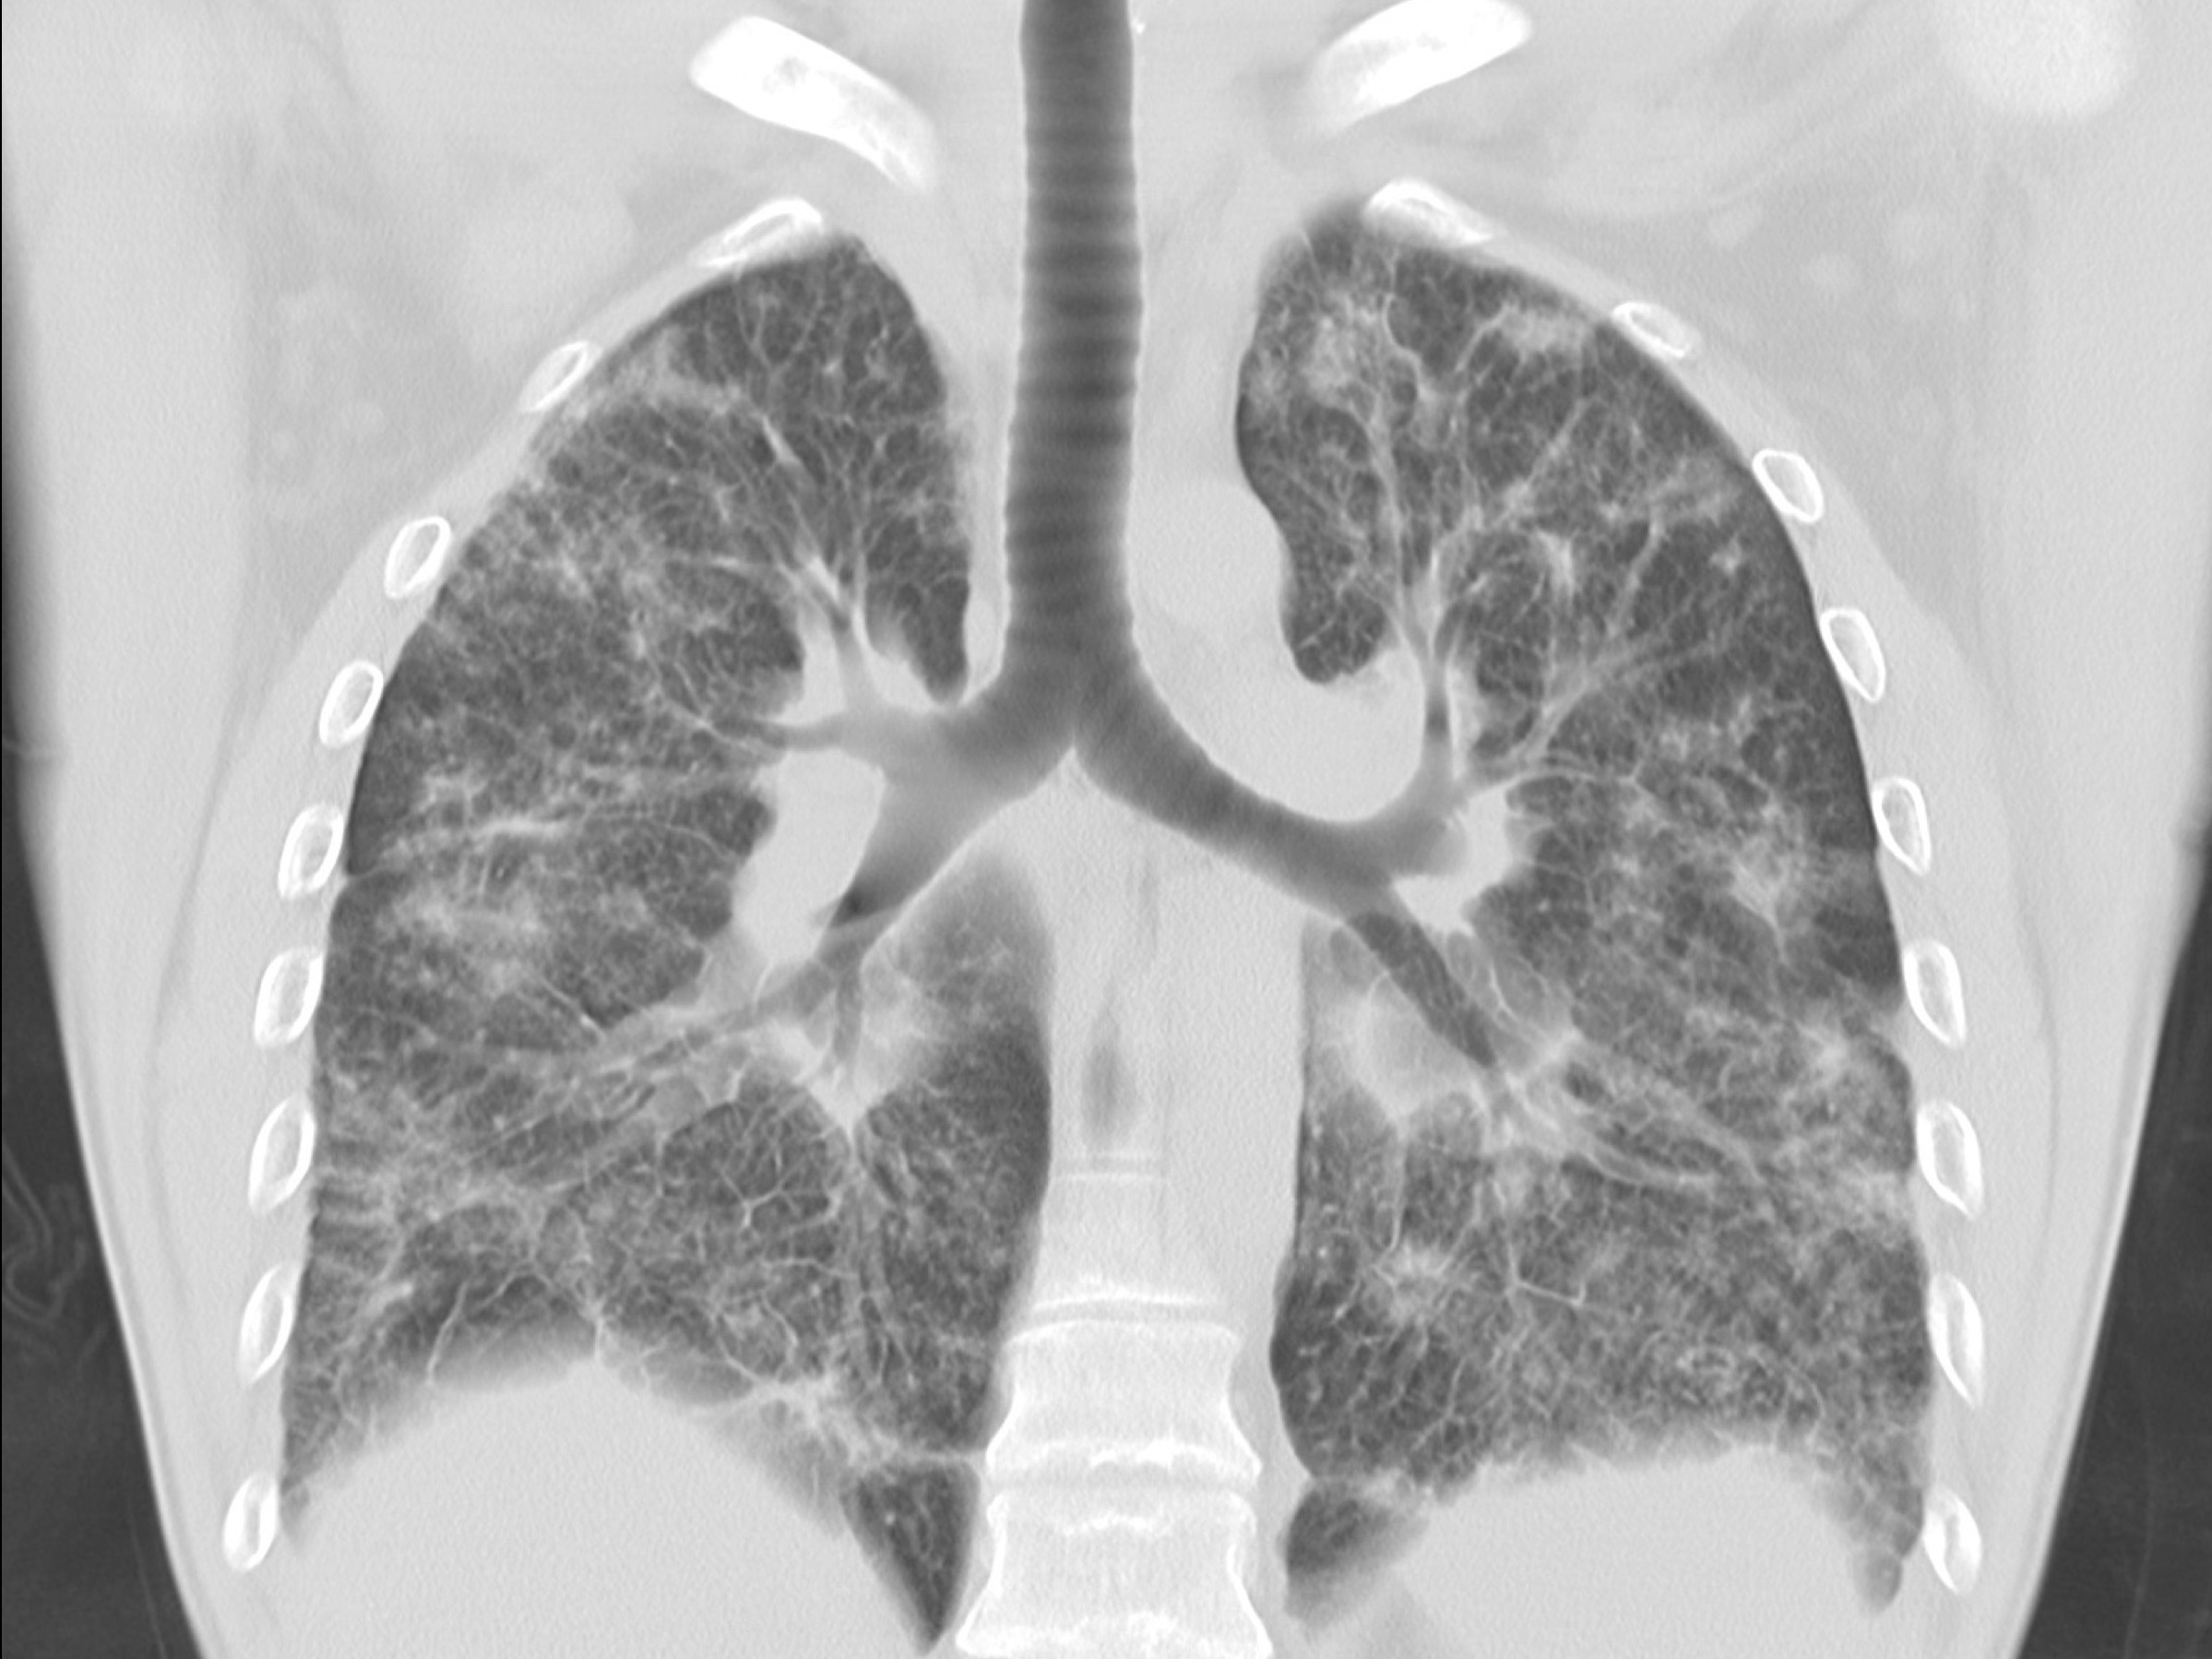

Рентгеновские и МРТ снимки легких